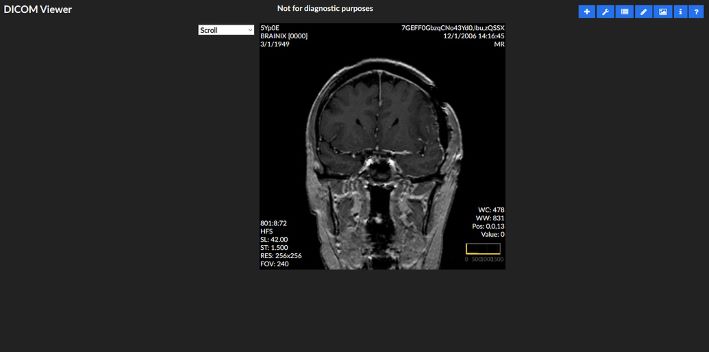

Introducing, the OpenEMR DICOM Web Viewer (DWV) by Jerry Padgett.

DICOM® (Digital Imaging and Communications in Medicine) is the international standard to transmit, store, retrieve, print, process, and display medical imaging information. DICOM®: makes medical imaging information interoperable. wikipedia It makes it possible for us to view and share radiology images in a computerized format and avoid having to carry around the hard copies. Because it standardized the formatting of the images, any computer may open and display the patient image making it possible for doctors to view and share information regardless of the computer operating system.

It is now possible to upload, store, and view digital radiology images from within OpenEMR, without needed additional software, simplifying medical decision making and thereby delivery of service at the point of care. Not to mention improving time and cost-efficiency.

The DICOM VIEWER will be available effective the OpenEMR version 5.0.4 release.